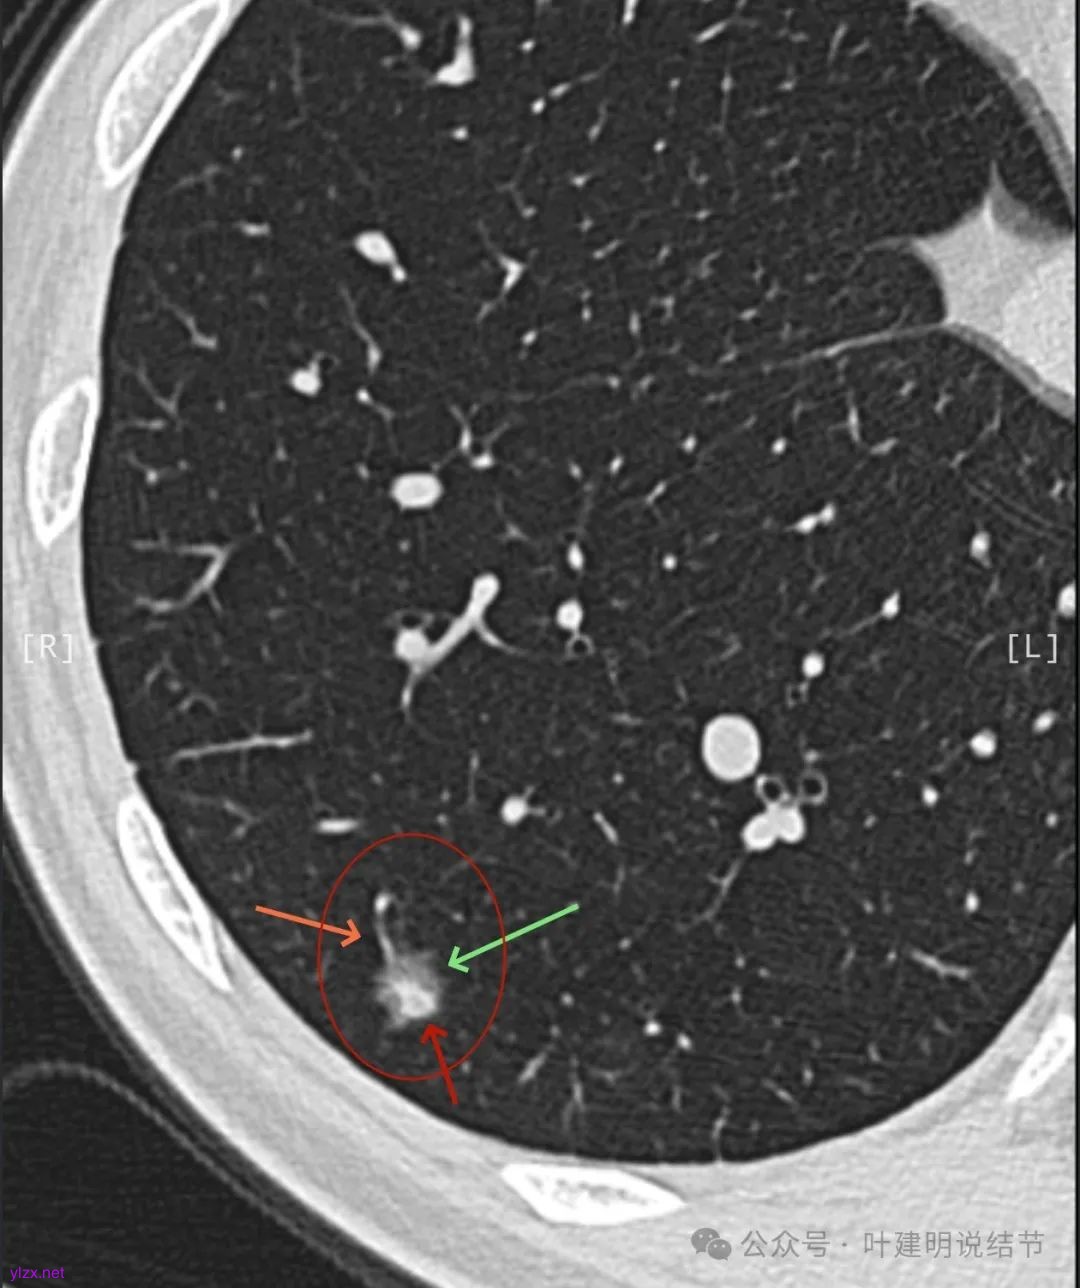

患者7年前在当地医院就诊时完善胸部CT发现肺结节,发现后未服用药物治疗,定期复查随诊,2024-09-29复查胸部CT提示:右肺下叶(薄234)见混杂密度小结节影,边缘毛糙,大小约0.8x0.7cm,其内见小血管穿行。双肺可见多发微小结节影,双肺见索条影,右肺可见小钙化灶。近期患者无咳嗽、咳痰、咯血、胸闷、胸痛、心慌、气急、头晕、头痛、畏寒、发热等不适,精神、饮食、睡眠正常,大小便正常,体重无明显变化。

2024年9月时病灶较前有所增大,实性成分增大,表面不平,棘突明显,进入血管有异常增粗。

右下叶混合密度结节,随访略有进展,表面不平、边缘毛刺,有血管进入,整体轮廓与边界清,考虑是肿瘤范畴的,从进展缓慢来讲,恶性程度不高,应该是微浸润性腺癌或浸润性腺癌含贴壁与乳头型可能性大。由于位置好,能楔切,倾向考虑单孔胸腔镜下局部切了。意见供参考!